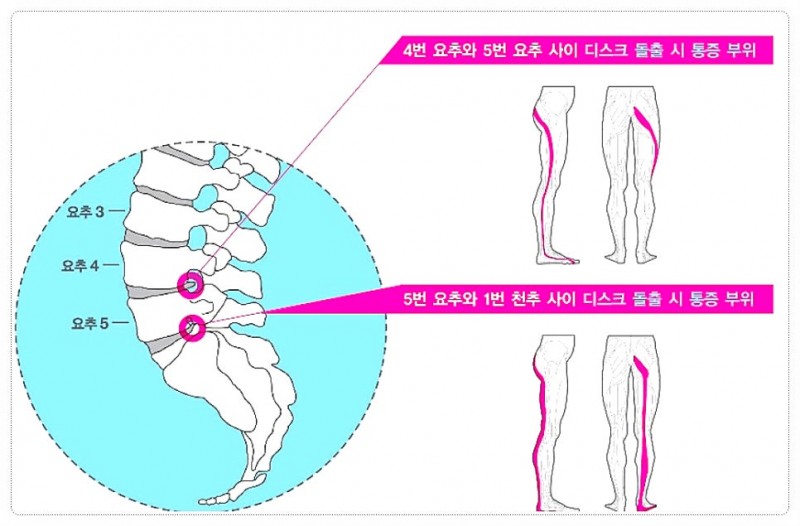

특히 요추 3번, 4번, 5번 부위는 우리 몸의 하중을 가장 많이 견디는 곳이라 압력이 쏠리기 쉽습니다.

이 과정에서 요추 3, 4, 5번 디스크는 원래 견뎌야 할 무게보다 훨씬 무거운 압력을 받게 되죠.

특히 허리만 아픈 게 아니라 엉덩이를 지나 다리까지 저릿저릿하게 내려오는 느낌은 겪어보지 않은 사람은 모를 큰 고통이죠.